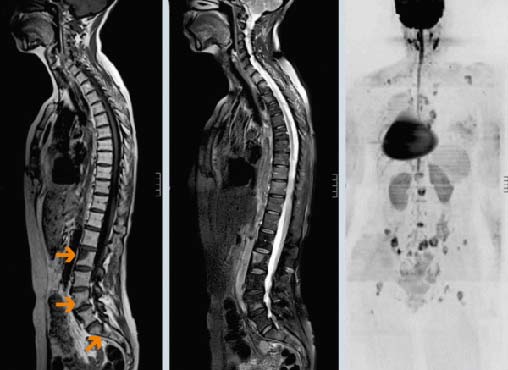

Основные методы диагностики — КТ и МРТ. Они помогают детально визуализировать структуры позвоночного столба, опухолевую ткань. Рентгенография менее информативна, так как на снимках видны только костные структуры, обычно ее применяют при подозрении на патологический перелом.

- Магнитно-резонансная томография (МРТ);

- Сцинтиграфия – введение радиоактивного вещества, посредством которого на компьютере можно зафиксировать функциональное состояние исследуемого органа и увидеть как выглядят патологические изменения в нем.